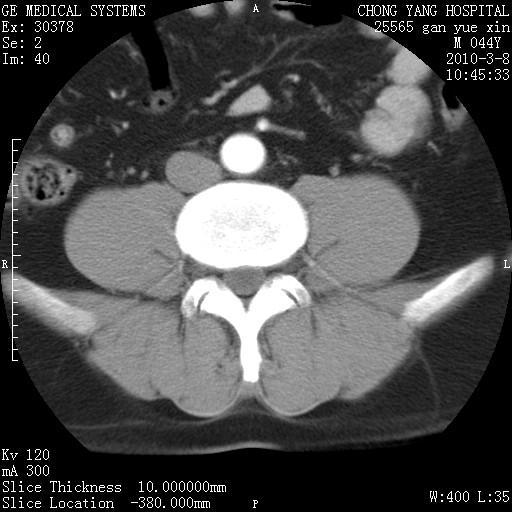

标题: CT24940:主动脉增强,典型病例。 [打印本页]

标题: CT24940:主动脉增强,典型病例。

夹层动脉瘤。

动脉夹层

夹层动脉瘤,典型

主动脉夹层。

动脉夹层的分型:

⒈debakey分型:根据主动脉夹层累及部位,分为三型:ⅰ型:原发破口位于升主动脉或主动脉弓部,夹层累及升主动脉、主动脉弓部、胸主动脉、腹主动脉大部或全部,少数可累及髂动脉。ⅱ型:原发破口位于升主动脉,夹层累及升主动脉,少数可累及部分主动脉弓。ⅲ型:原发破口位于左锁骨下动脉开口远端,根据夹层累及范围又分为ⅲa,ⅲb。ⅲa型:夹层累及胸主动脉。ⅲb型:夹层累及升主动脉、腹主动脉大部或全部。少数可累及髂动脉。

⒉stanford分型:a型:夹层累及升主动脉,无论远端范围如何。b型:夹层累及左锁骨下动脉开口以远的降主动脉。

夹层动脉瘤,少量胸水

夹层动脉瘤;左侧少量胸腔积液。

典型主动脉夹层。